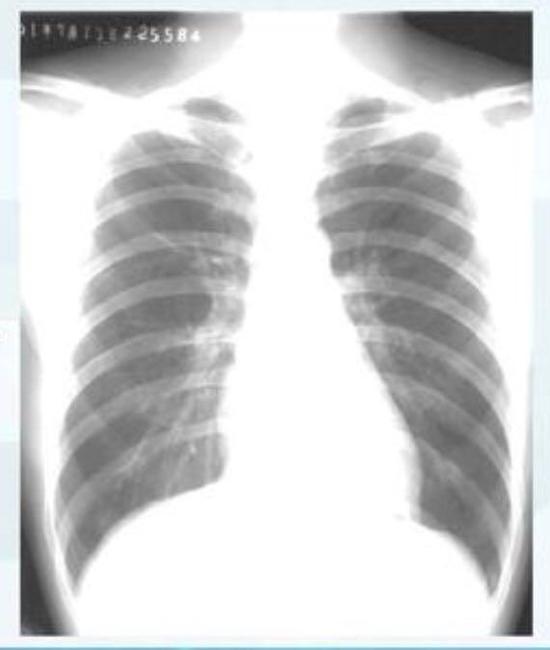

▲正常情况下人的肺部CT表现(图片来自网络)